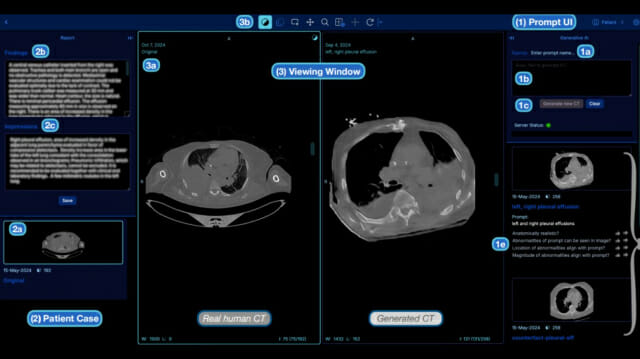

“말 한마디로 CT 촬영 완성”…AI 의사들이 직접 써본 결과는

[지디넷코리아] 미국 카네기 멜론 대학교 연구팀이 흥미로운 실험을 진행했다. “오른쪽 폐에 물이 찼고, 왼쪽 아래쪽 폐는 정상”이라고 글로만 적으면 해당 상태의 CT 사진을 만들어주는 AI를 개발한 것이다. 실제 […]